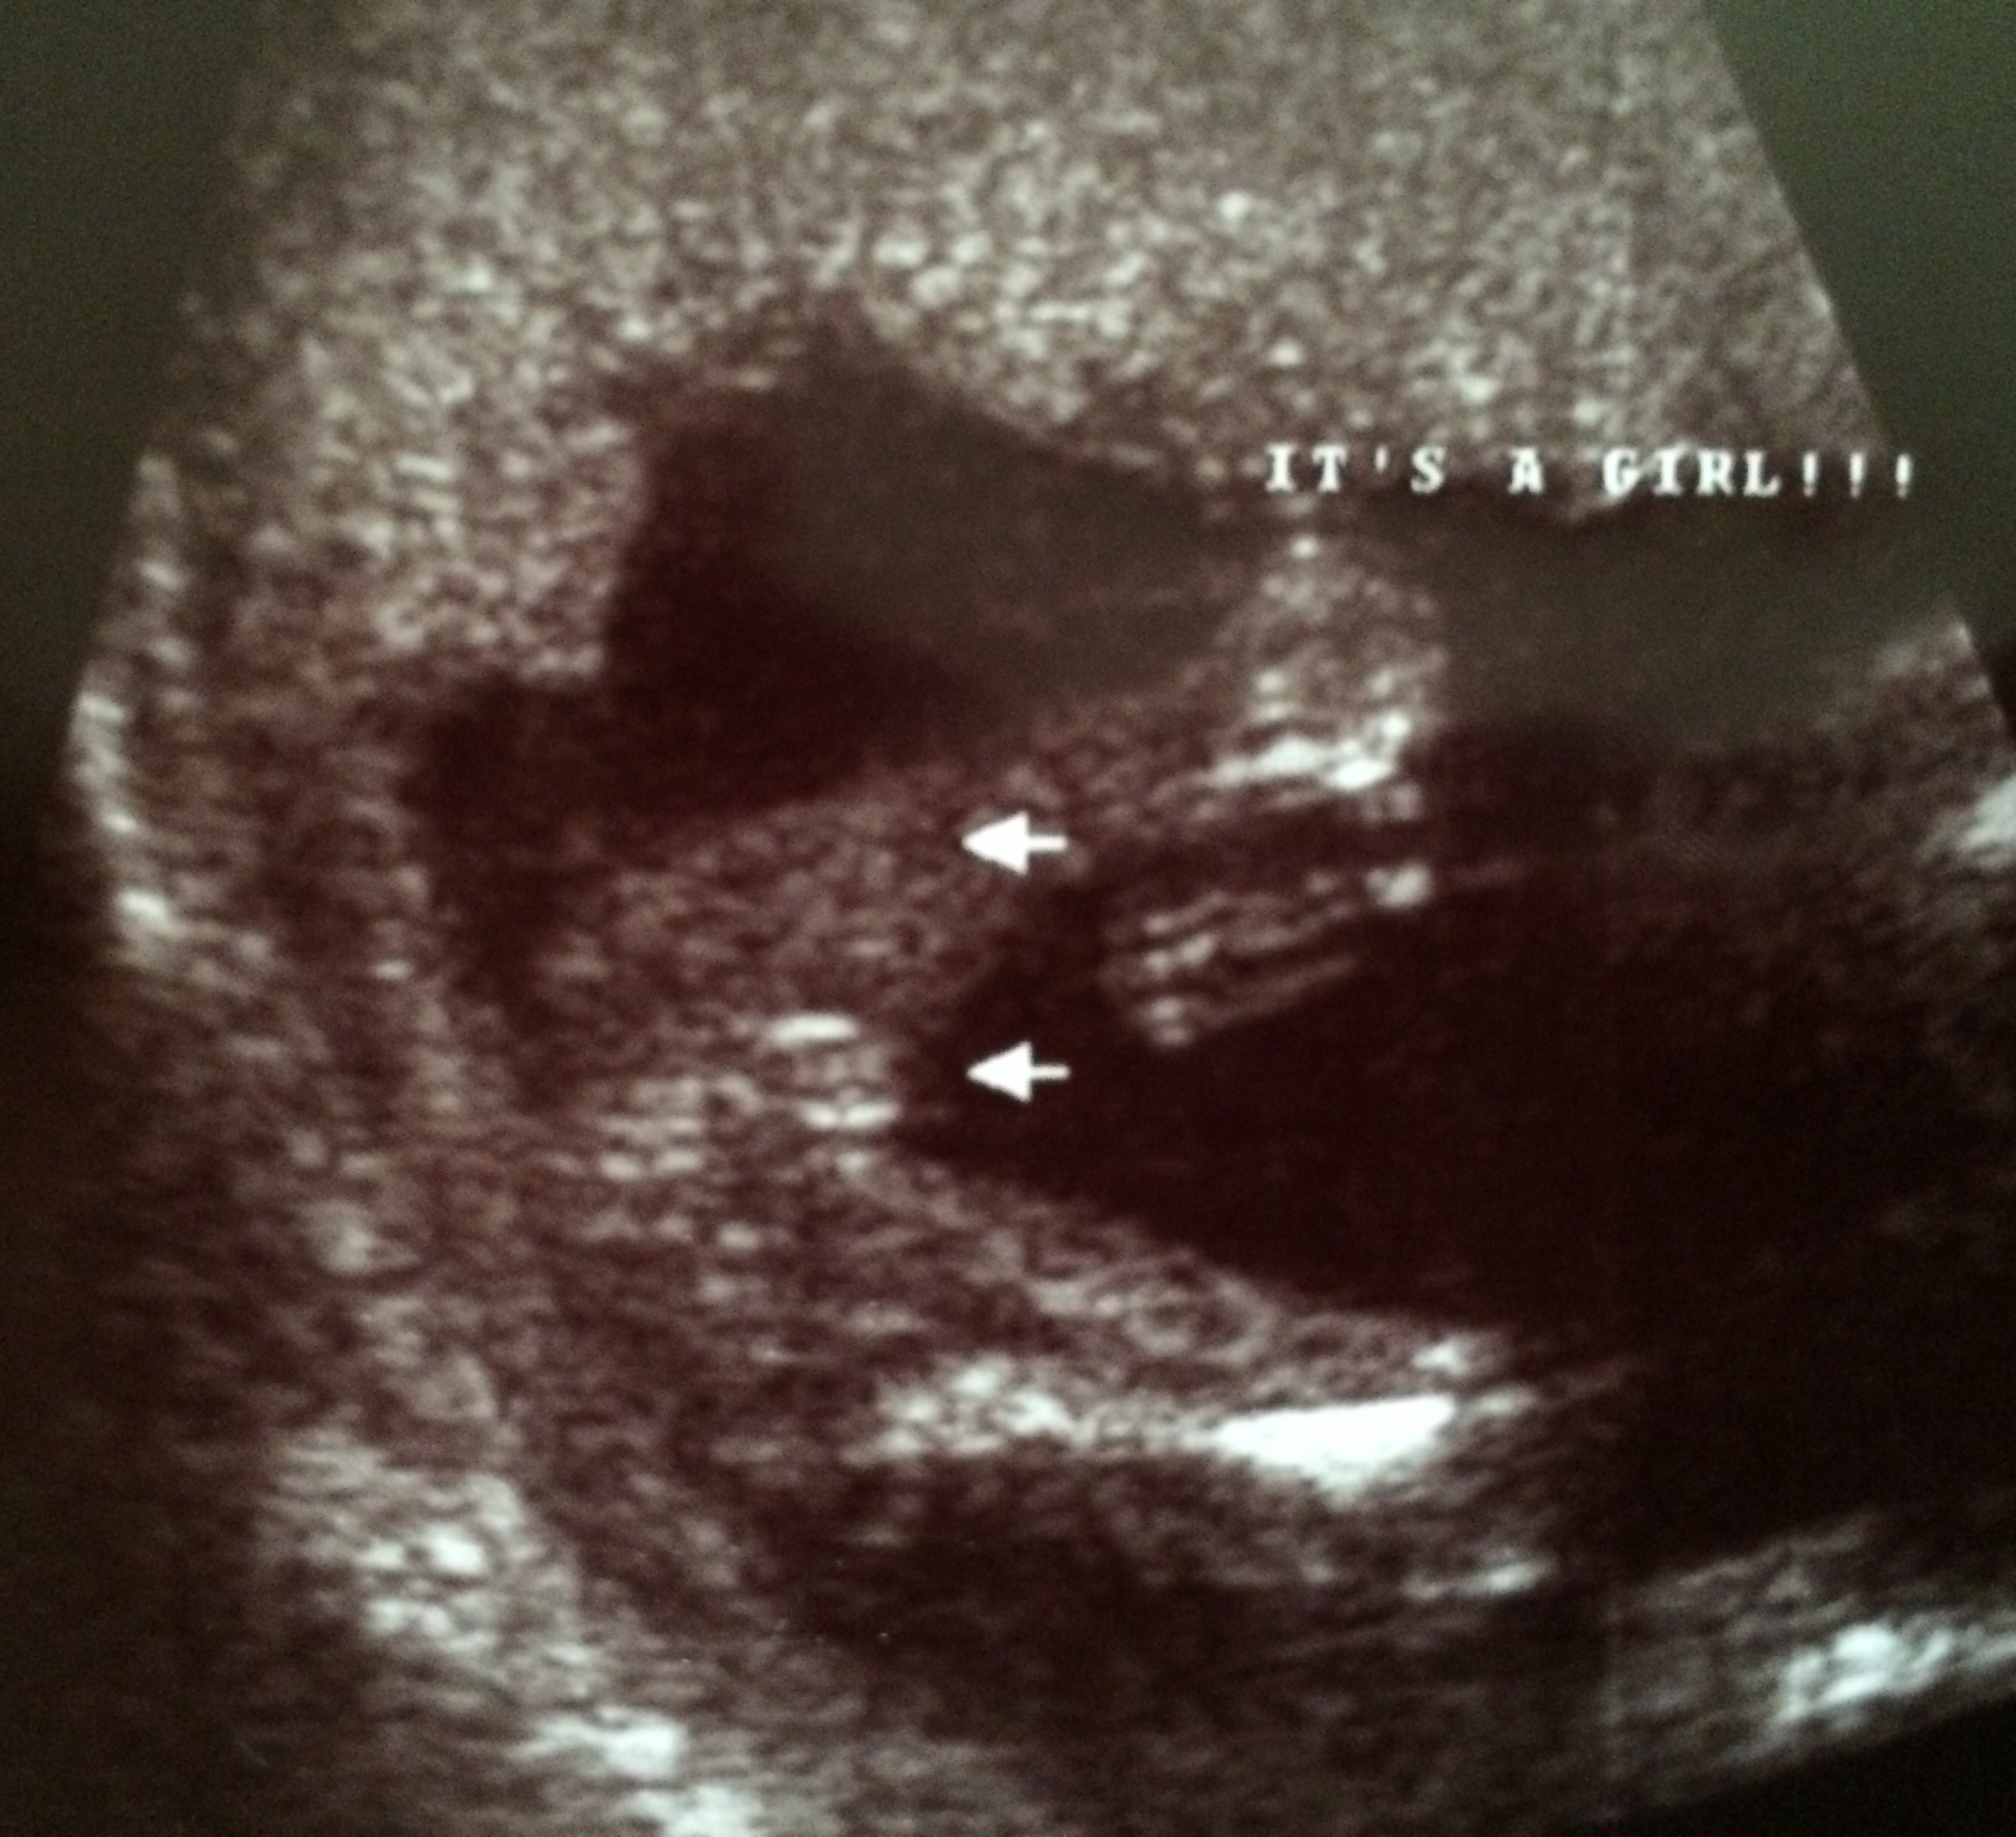

We got a private scan at 16 weeks 5 days. The ultrasound tech said she was 100% sure it was a girl. But for some reason I'm still freaking myself out. His mom has bought so many girl clothes already ( first grandchild ) I'm now 21 weeks and I go in 2 days for my anotomy / growth scan, which I know they don't really focus that much on gender like they would with a private scan. I would just like some other mommies opinions for comfort!!! ☺️ thanks !

• Looks like a girl! Congrats!

• Congrats!! It looks like a girl to me.

• I'm an X-ray tech not ultrasound but that looks like a girl to me!

• Girl.